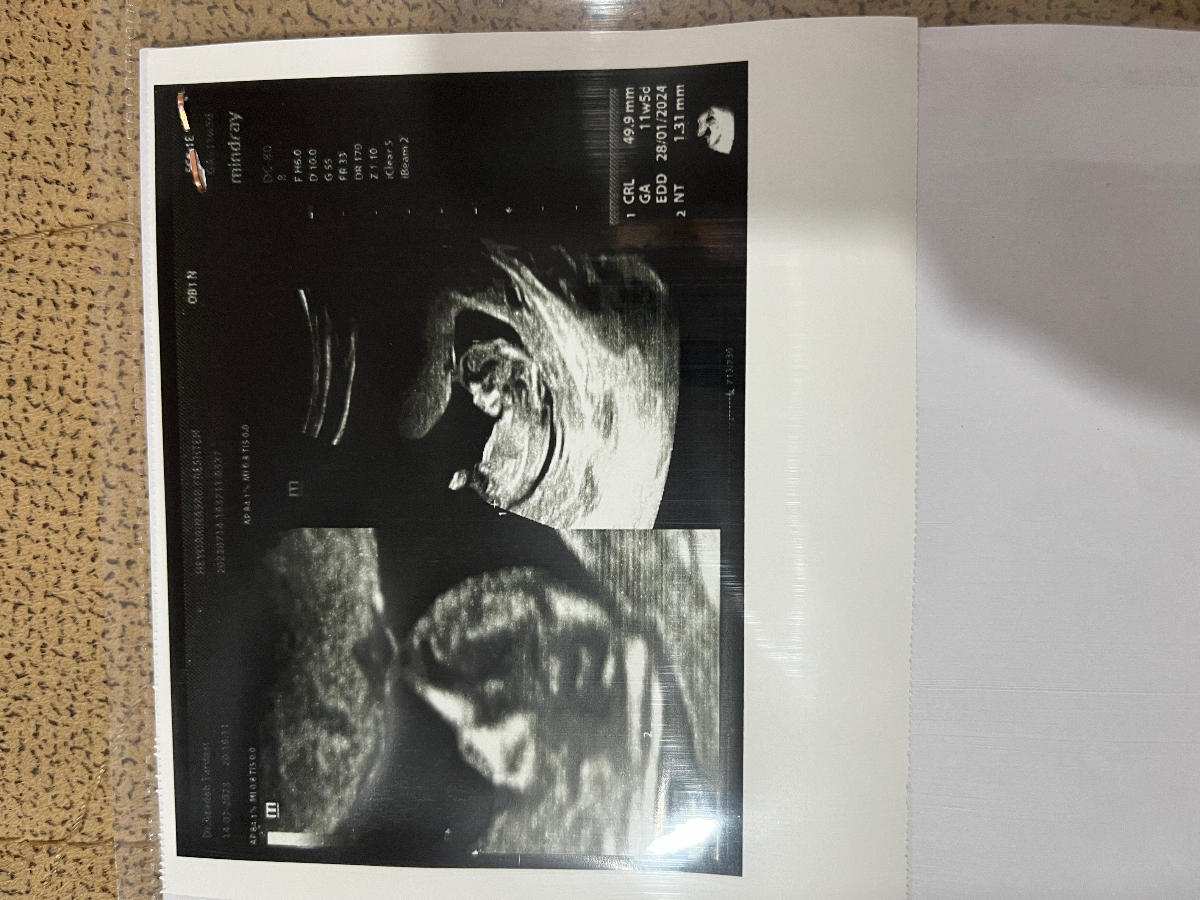

سلام دوستان بچه ها میشه اگه امکان داده عکس ان تی هاتون بفرستید بگید نی نی تون چیه یا کسی وارده جنسیت نی نی منو بگه برا خودم فرق نمیکنه ولی دوست داشتم به خاطر شوهرم یه پسرم داشته باشم چون دیگه بچه نمیخواستم چون دکترم گفت از رو ستون فقرات اینا به دختر میخوره .

من حدس میزنم اقا پسر باشه عزیزم

حس میکنم پسره

پسره انگار

جمجمش بیشتر ب پسر میخوره

به من 11هفته پنج روز احتمال پسر دادن ولی دختر بود

13هفته کاملا مشخص شد دختره اگه میخوای میتونی هفته ی دیگه بری واسه جنسیتش

اره جمجه اش و حالت پاهاش مثل پسرهاس

اخه عکس سونو گرافیت شبیه عکس بچه منه من احتمال زیاد میدم پسره انشالله